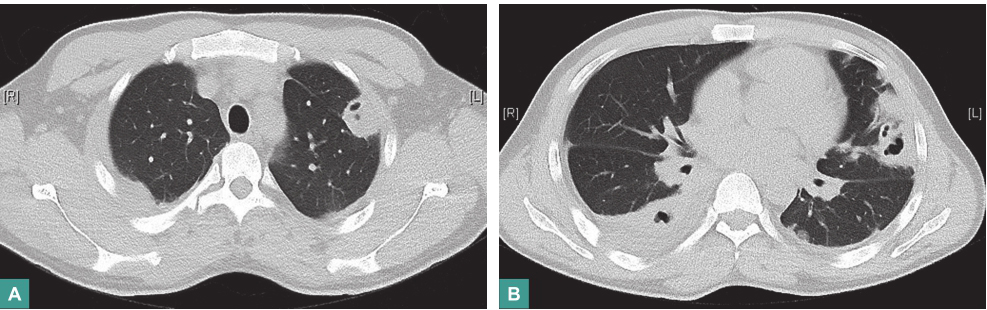

例如金黄色葡萄球菌感染引起的血源性肺脓肿(图2),患者多存在寒战、高热等全身中毒症状,伴有咳嗽、咳黄脓痰,实验室检查提示血象明显增高。

图2 关节腔感染继发金黄色葡萄球菌肺脓肿胸部影像学表现

胸部CT可见双肺多发高密度斑片状实变影,其间可见坏死性空洞改变